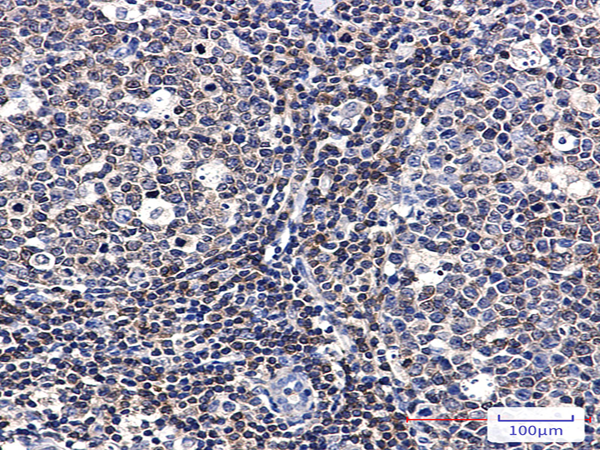

| IHC positive control: | Human tonsil |

| IHC Recommend dilution: | 50-100 |